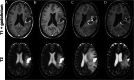

Results: We identified 11 patients who had received a singular administration of bevacizumab to treat cerebral radiation injury. Prior radiation had been administered to treat gliomas (ten patients) or breast cancer brain metastases (one patient). 9 of 10 patients with available MRIs showed a marked reduction of edema at first follow-up. Discontinuation of Dexamethasone was possible in 6 patients and a significant dose reduction could be achieved in all other patients. One patient developed pulmonary artery embolism 2 months after bevacizumab administration. The median time to treatment failure of any cause was 3 months.